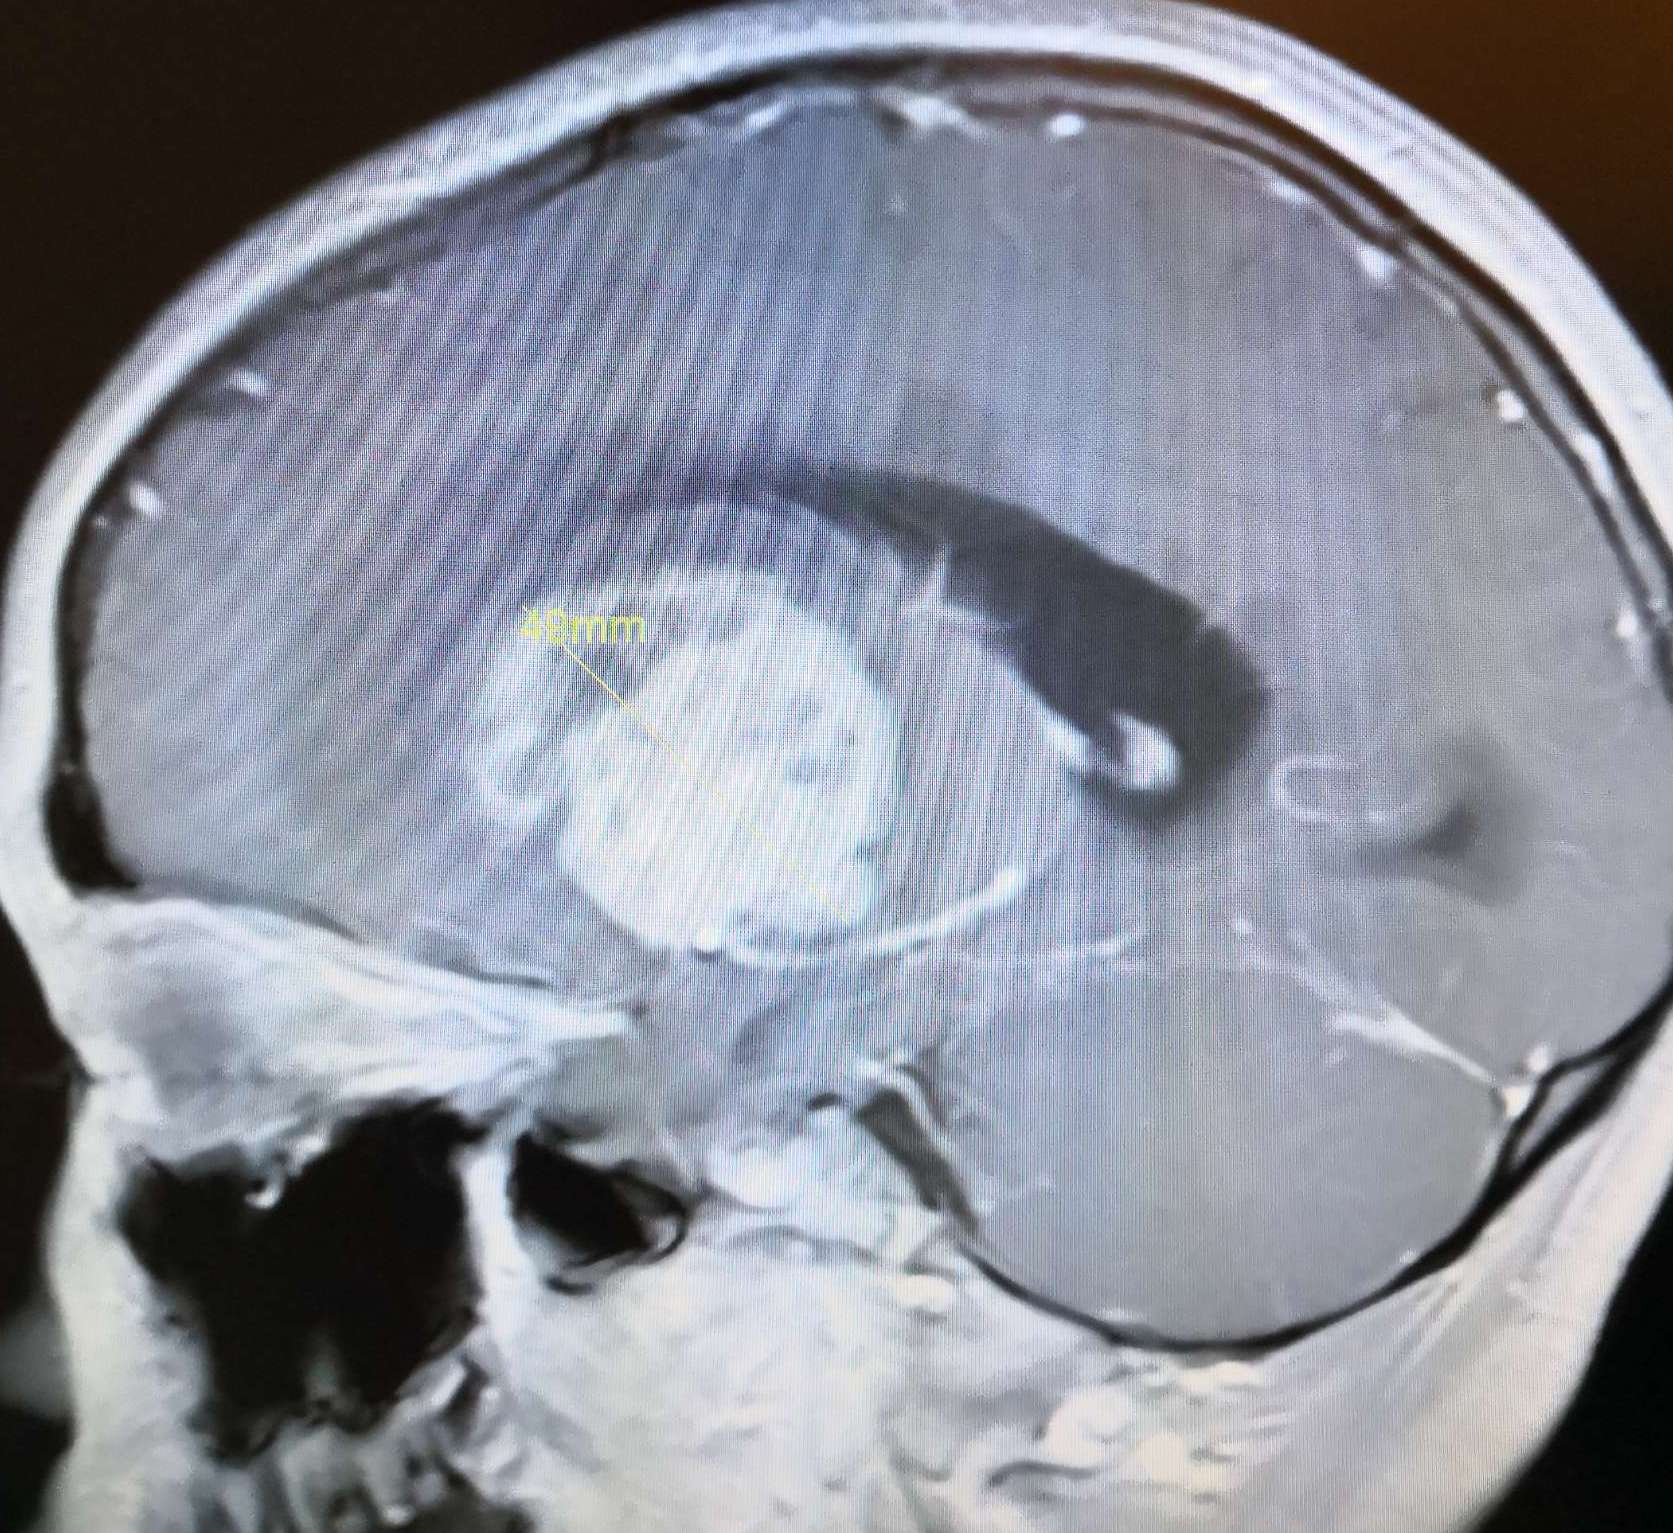

术前头颅MRI增强扫描显示:病灶强化明显,脑室受压,中线移位明显。

术前头颅MRI 增强扫描显示:病灶强化明显,脑室受压。

术前头颅MRI 增强扫描显示:病灶强化明显,脑室受压,中线移位明显。